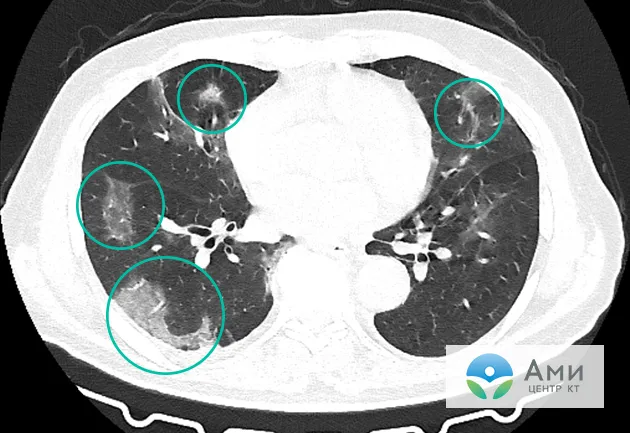

Как визуализируется повреждение легких от вейпинга на КТ

Повреждение легких в результате вейпинга и электронных сигарет

Повреждение легких на КТ при EVALI выглядит как пневмония. Оно определяется по симптомам «матового стекла» (очаги инфильтрации и уплотнения легочной ткани), локализованным в основном вокруг бронхов. Часто наблюдаются консолидация и затемнение. Чаще всего страдают нижнедолевые и субплевральные области легких — симметрично с обеих сторон.